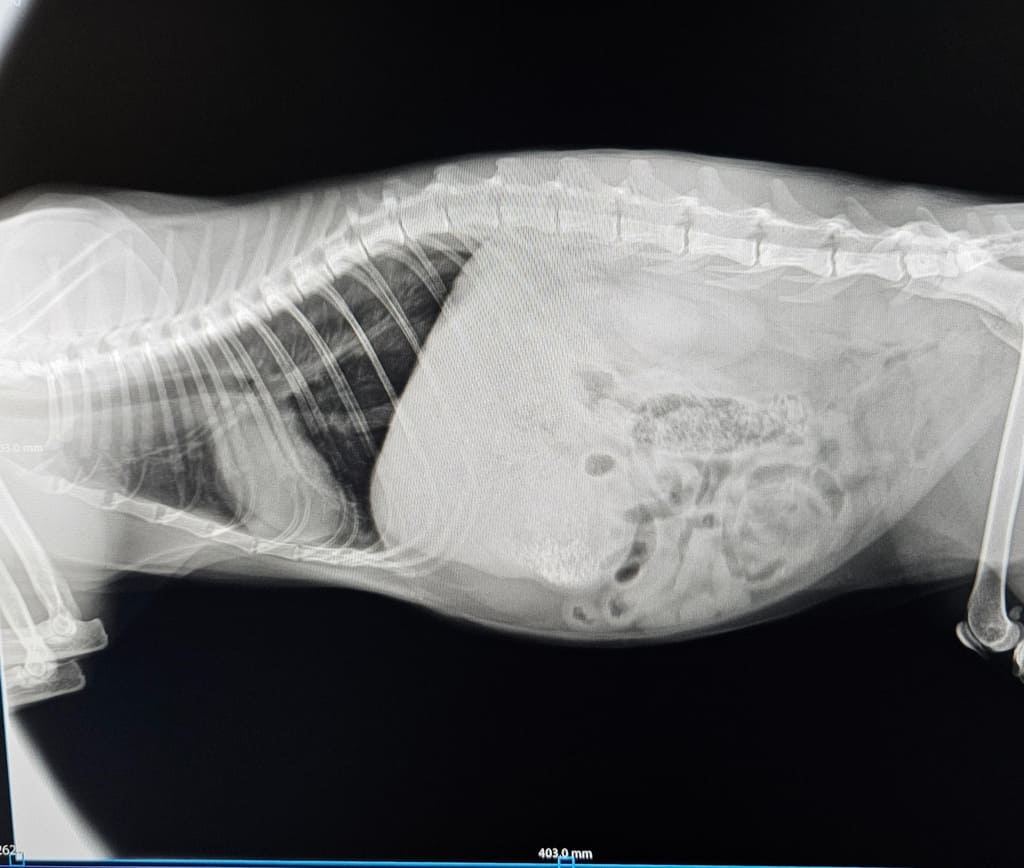

Le condizioni del povero micio

Il micio trovato investito e abbandonato in strada dovrà subire un intervento. Ha anche la vescica lacerata. Abbiamo bisogno di soldi, da soli non possiamo farcela, la cifra è alta.